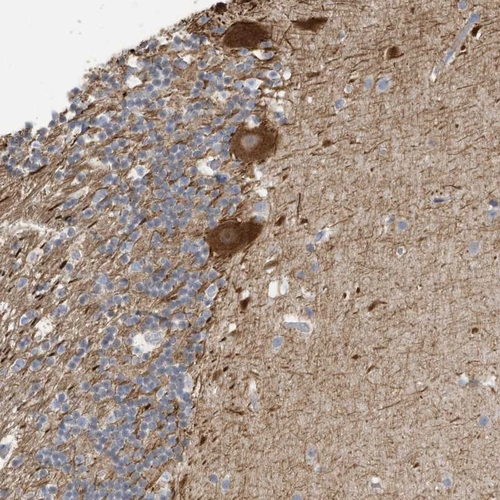

Immunohistochemical staining of human cerebral cortex shows moderate to strong cytoplasmic positivity in neuropil.